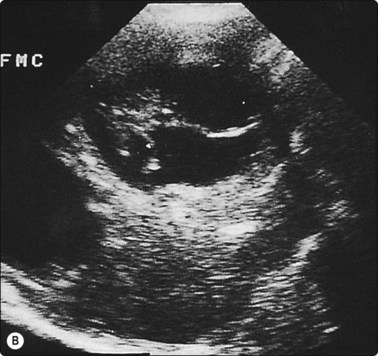

Fine needle biopsies of liver lesions, including hydatids and hemangiomata, are safe provided the needle passes through normal liver tissue to act as a seal (Fig. 3.10).

image image

Fig. 3.10 Aspiration biopsy of hydatid disease without complication

(A) Two clearly defined anechoic cysts within the liver. The more anterior cyst (**) was completely aspirated without complication. (B) Five months later the patient was rescanned and multiple loculi within the cyst provided the diagnosis of hydatid disease. This was confirmed at surgery.